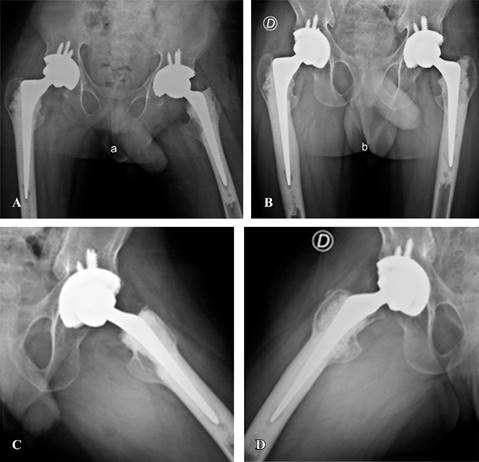

En el último control postoperatorio (26 meses de la ATC derecha y 25 de la izquierda), el paciente realizaba marcha sin asistencia y sin dolor, necesitando de un bastón eventualmente para largas caminatas. La puntuación de la EVA de dolor de ambas caderas fue de 0 y el HHS fue de 72 para la cadera derecha y 74 para la izquierda. El paciente refirió estar muy satisfecho con el procedimiento, fundamentalmente por la ausencia de dolor y por haber recuperado la independencia para actividades de la vida cotidiana. Refiriendo, además, que esto le permitió retomar la asistencia a diferentes actividades y reuniones sociales. Estos cambios en la calidad de vida del paciente se denotan en las puntuaciones del SF-36 registrado en el último control (Tabla 1). En el último análisis radiográfico, observamos los componentes protésicos en correcta posición, sin radiolucencias ni otros signos de aflojamiento protésico (Figura 4).

Figura 4: A) Radiografía anteroposterior de ambas caderas en el postoperatorio inmediato luego de la artroplastía total de cadera (ATC) izquierda y un mes de la derecha. B-D) Radiografías anteroposterior y lateral de ambas caderas a los dos años postoperatorios, sin signos de demarcación o aflojamiento.